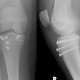

Am 15. November erschien die zweite Auflage des Patientenmagazins „Medizin mit Durchblick“. In dem Magazin geht es darum den Patientinnen und Patienten die Welt der Radiologie näher zu bringen. Auch die erste Auflage war ein voller Erfolg, weiter Informatienen finden Sie in diesem Artikel.